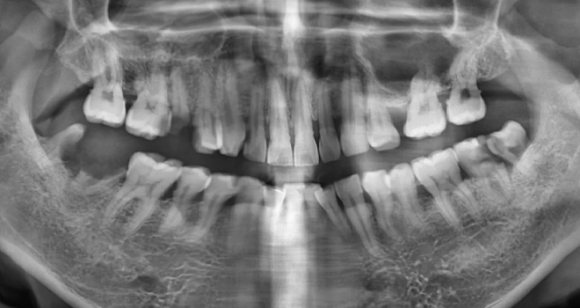

(치료 전) 파노라마

(치료 후) 임플란트,보철 등 여러 치료